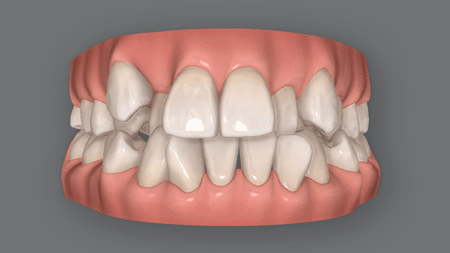

矯正後に、老け顔になる?

「矯正したらやつれてしまった」「疲れた感じで老けてみてる」このようなネット上のクチコミを見て、不安になっている方も多いかもしれません。

前歯を引っ込めすぎて

老け顔

矯正治療では、前歯をきれいに並べるスペースを確保するために、抜歯が必要なことがあります。

具体的には前から4番目の歯を抜いて、前歯を奥側へ引っ込めるスペースを生み出すのですが・・・。

この時に、前歯を口の奥の方へ動かしすぎると、皮膚が余ってほうれい線が深くなったり、頬がこけたり、口周りにシワができることがあります。

これが老け顔の原因です。そうならないためには、前歯だけでなく奥歯も少し前に動かして、スペースを埋めることが必要。

前歯をどこまで引っ込めるか、奥歯をどこまで手前に動かすのか、極めて高いスキルと経験が求められるのです。